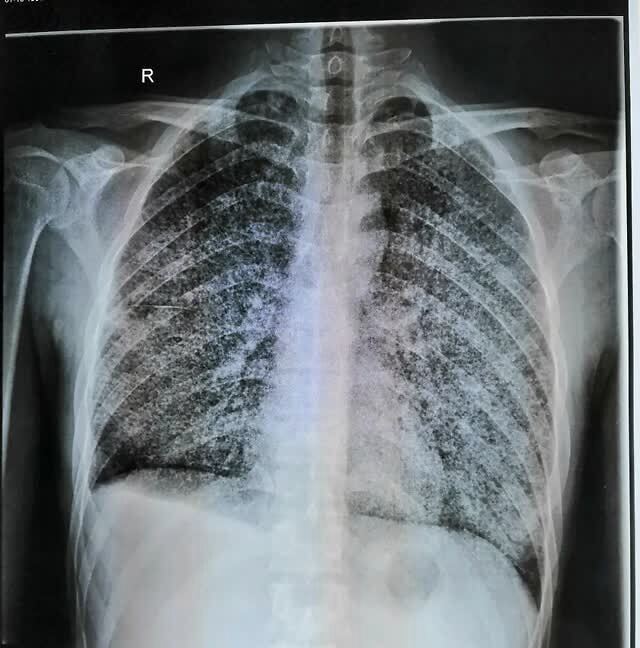

男性66岁咳嗽咳痰2日dr示双肺结核感染